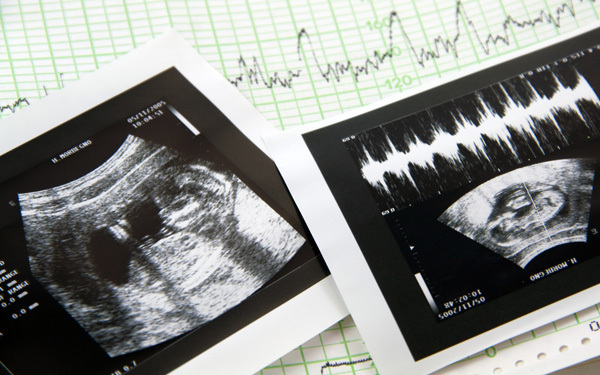

妊娠10ヶ月のエコー(超音波)写真

妊娠36週のエコー写真

赤ちゃんは子宮内で自由には動けないように。また、この頃の超音波検査は、通常の赤ちゃんの成長ぶりを確認するとともに、逆子などの理由で帝王切開になる可能性はないか、赤ちゃんの下がり具合や子宮の収縮などでお産が近づいているかなど、お産の進み方を推測します。

臨月になると体の一部しか見えません。成長の具合を最終チェックします。

この頃になるとエコー写真に写るのは体の一部だけ。大きな口を開けている横顔がくっきりと見えます。